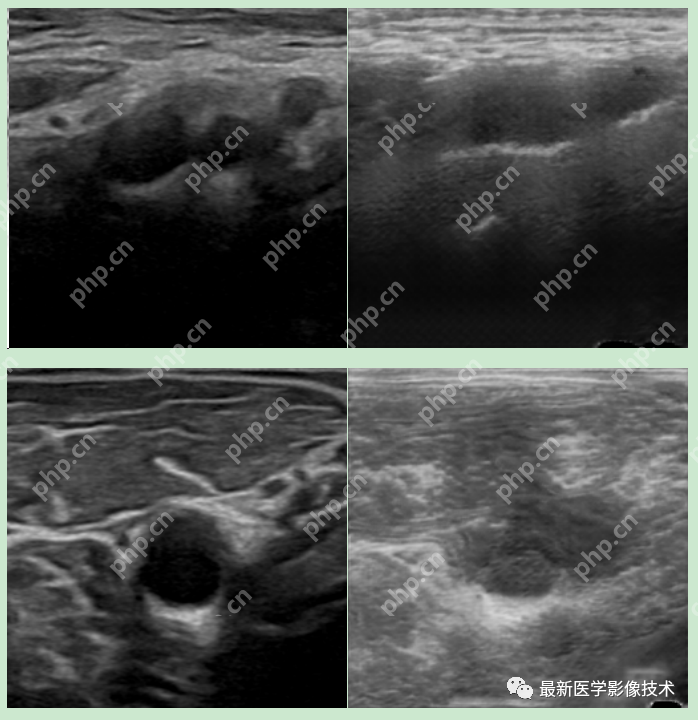

6、测试集部分生成结果

左图为低质量图像,右图为生成的高质量图像。